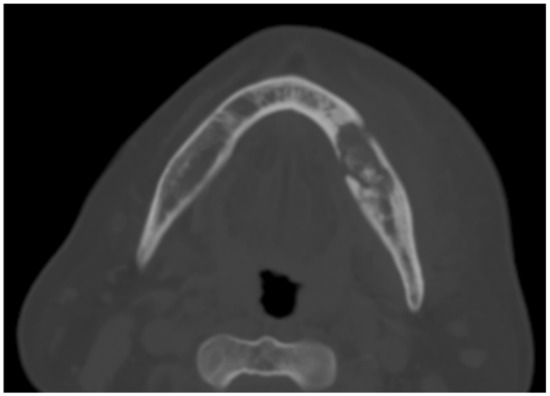

| No | Age (y) | Sex | Primary Disease | Details of RT | Smoker | MH | Stage * | Max/Mand | Site | Procedure | Follow-Up | Outcome |

|---|---|---|---|---|---|---|---|---|---|---|---|---|

| 1 | 67 | M | Adenoid cystic carcinoma left parotid gland | CCRT 33# (Cisplatin) EBRT 5# | No | BPH, ED | 1 | Mand | 36, 37 | Multiple extraction of 36, 37 with PRF application and PC | 3 years | Healed |

| 2 | 64 | M | SCC right lateral border of tongue | CCRT 35# (Cisplatin) | Yes | AF, COPD, IHD, DLP | 2 | Mand | 41 to 43 | Sequestrectomy, autologous free fat graft transplant, PRF application | 4 years | Healed |

| 3 | 54 | M | Nasopharyngeal Carcinoma | CCRT (Cisplatin, 60Gy, 30#) | No | HPT, DLP | 1 | Mand | 34, 44 | Multiple extraction, sequestrectomy, PRF application and PC | 3 months | Healed |

| 4 | 66 | F | Right tonsillar carcinoma | CCRT (Cisplatin, 60Gy,30#) | No | HPT | 2 | Max, Mand | 16, 47 | Multiple extraction, sequestrectomy, PRF application and PC | 3 years | Healed |